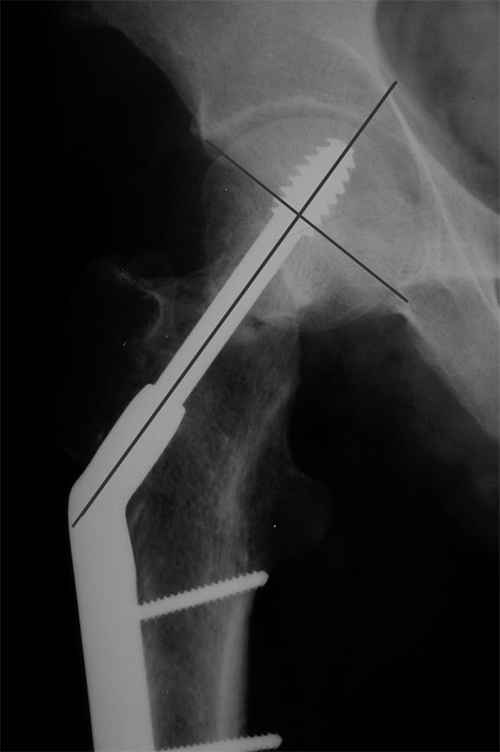

Больной Т. 1966 г.р.Травма 28.06.2007. Прооперирован в г. Бишкек, Оп: Остеосинтез правого бедра системой DHS. В последующем беспокоили периодические боли в правом тазобедренном суставе с иррадиацией в коленный сустав в область передней поверхности правого бедра. Лечился амбулаторно с незначительным эффектом. В 07.04.2008 по 08.05.2008 года лечился в госпитале ГУВД и СО в стационаре с Срастающийся перелом шейки правого бедра в условиях фиксации системой DHS – боли уменьшились.Боли обострились 03.02.2009 внезапно, госпитализирован. Результат - Псевдоартроз шейки правого бедра (имеются косвенные признаки разрушения спонгиозной части головки бедра)Планируется - Работает милиционером. Имеющийся опыт протезирования у данной категории во всех случаях в ближайшее время заканчивался дисквалификацией. Работоспособный возраст (43 года).Наиболее приемлемым и реальным методом лечения предполагается: Удаление конструкций из бедра. Заполнение полости от винта монолитным аутотрансплантатом из крыла (крылев) подвздошной кости. Медиализация большого вертела. Предполагаемый период нетрудоспособности 3-4 мес.

На более раннем снимке репозиция была, мягко говоря, далека от идеальной. Плюс перелом шейки слишком проксимальный для фиксации одном винтом. Неудача тут закономерный исход.

И, видимо, вальгизирующая остеотомия бедра - если в планах все-таки продолжать попытки сохранить собственный сустав. Эндопротезирование более предсказуемый путь.

Но в данном случае DHS сыграл как имплант с угловой стабильностью, что привело к прорезыванию импланта в верхнем сегменте головки. Отсутствие трехточечной опоры и длинный имплант увеличивают нестабильность в шейке.

Коллеги правы, что надо делать вальгусную остеотомию с латеризацией диафиза бедра. Рекомендуемая медиализация приведет к вальгусной деформации оси конечности.

Предлагамый монолит из-за трудности проведения Special Chisel для клинка не рекомендуется. Место удаленной конструкции забивается спонгиозной костью из крыла, для предупреждения пенетрации в сустав лучше под экраном.